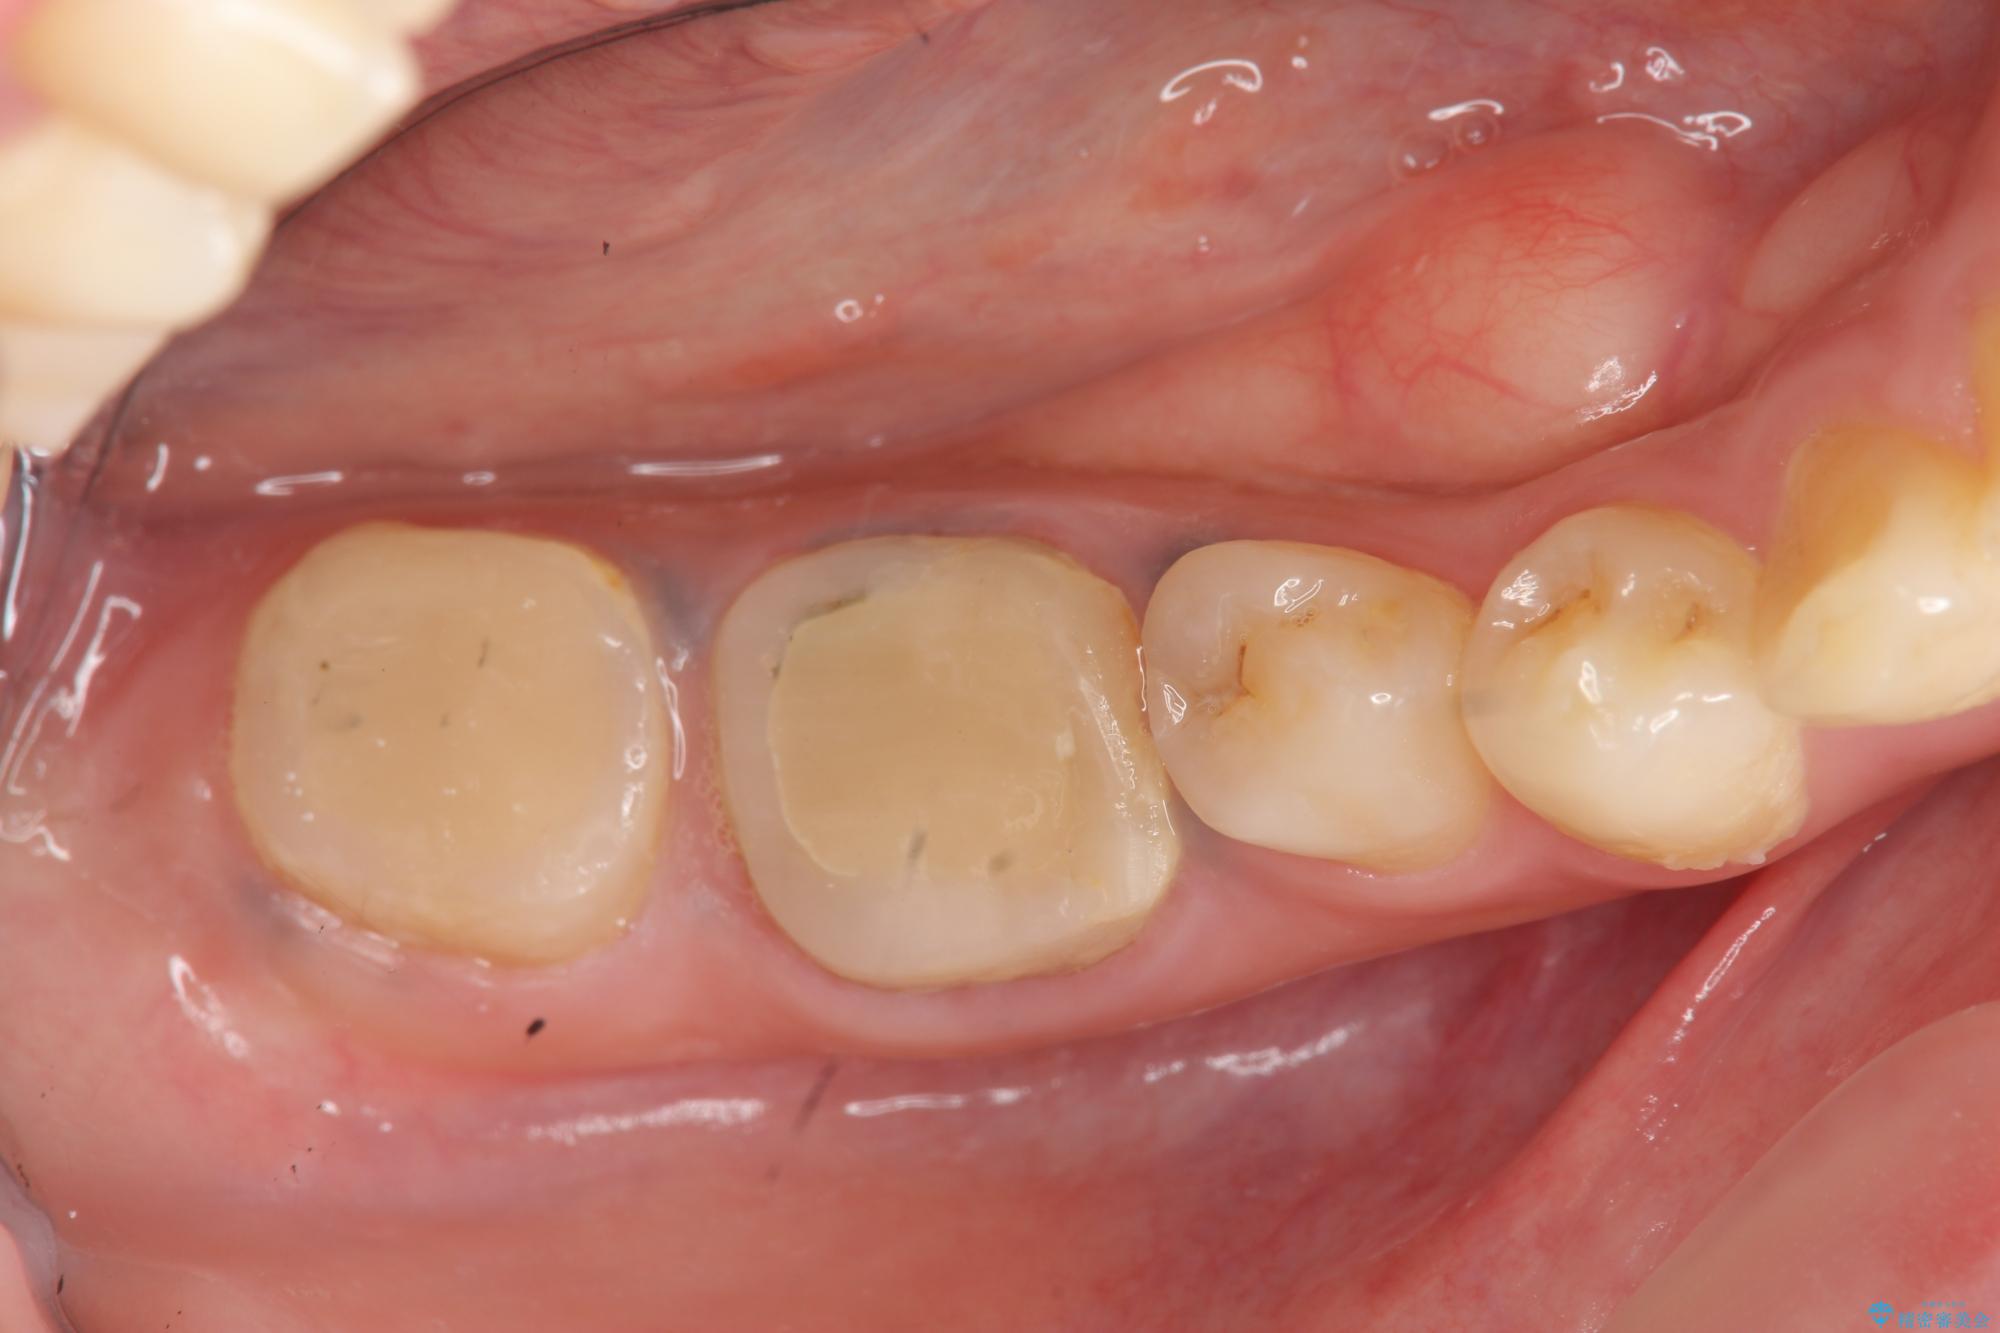

- 治療途中で放置してしまった奥歯の治療の続きを希望され来院されました。

奥歯は既に根管治療が為されクラウンを装着する必要性がある状態ですが、歯の高さが低くクラウンの安定性・強度を担保するために歯周外科を行う治療計画としました。

歯周外科を行うことで、歯ぐきの位置を下げ歯の高さを作り出し安定したクラウンの装着が可能となります。また同時に舌の邪魔となっていた骨隆起の除去を行うこととしました。